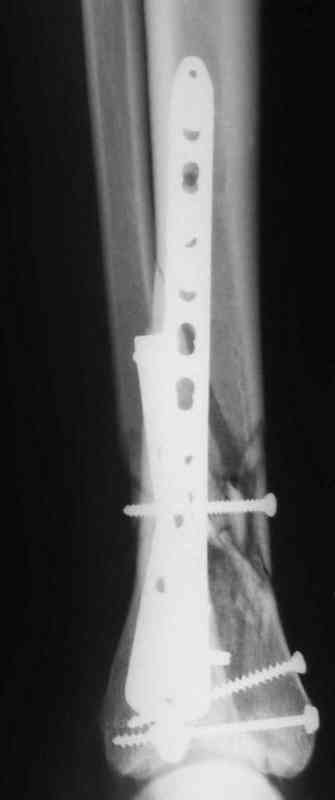

Re: Pilon

послал Дрягин В. 05 Январь 2007, 14:30

Да кстати нашёл похожий случай для пилона.Малоинвазивная дистальная пластина LCP у вас я думаю есть опыт их использования ну очень хорошая. Очень стабильно получается.